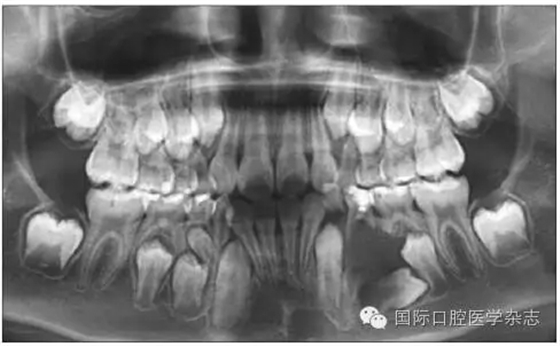

圖3為一因“乳磨牙爛牙”前來就診兒童的X線片檢查。影像學檢查顯示:第二乳磨牙近中深齲,近遠中牙根吸收均不明顯,但遠中根尖病變引起了第二前磨牙萌出方向的改變。臨床處置:及時拔除了齲壞的第二乳磨牙,制作第一恒磨牙帶環(huán)絲圈間隙維持器,3個月后復診,X線片顯示第二前磨牙萌出方向逐漸正向調整;6個月后復診,第二前磨牙基本正位萌出;1年后復診,第二前磨牙調整到位。從圖3的病例可以看出:乳磨牙根尖周病變會引起恒牙萌出方向的改變,出現咬合紊亂的潛在性表現,但臨床上通過去除病灶牙與簡單的間隙維持、未實施牽引助萌即糾正了該病例潛在性的咬合紊亂發(fā)生。

A:下頜第二乳磨牙近中齲,X線片顯示遠中根尖周病變引起繼承恒牙萌出方向改變;B:擬及時拔除病變的下頜第二乳磨牙,行間隙維持;C:拔除病變的下頜第二乳磨牙間隙維持后一段時間,繼承恒牙萌出方向發(fā)生正向改變;D:繼承恒牙正位萌出。

圖3 乳牙根尖炎癥引起繼承恒牙萌出方向改變的典型病例

Fig 3 Typical case oferuptive direction change caused by periapical infection of primary tooth